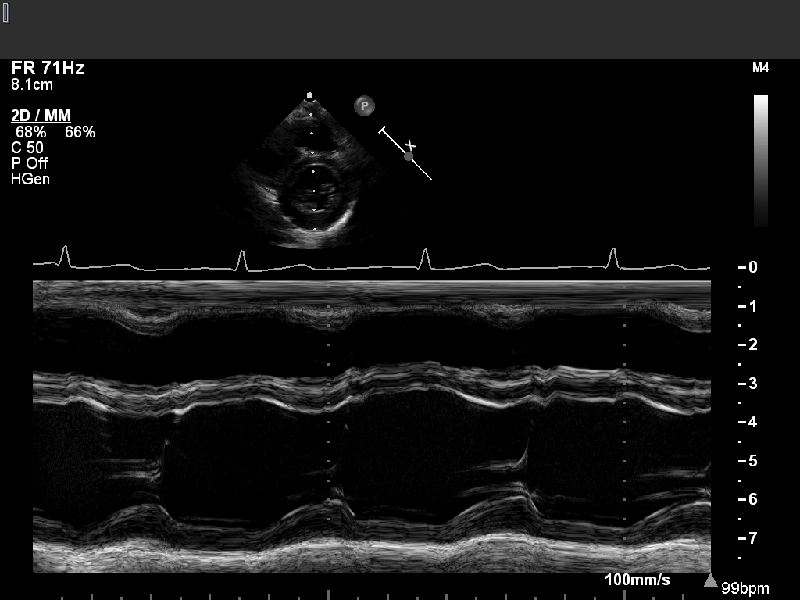

- Echo images can be acquired as single 2D images (still frames, Figure 1), video (a series of frames acquired in rapid succession), or “M-mode” (the signal from a single line repeated very rapidly in order to monitor motion of particular structures).

M-mode (or “motion-mode”) imaging is an implementation of cardiac ultrasound in which the data from a single scan line is plotted versus time, as shown in Figure 2. Currently, the 2D image shown at the top of the figure is used as a guide to select the single scan line of interest, but historically, M-mode imaging was developed before 2D imaging and was adjusted by the operator based on the visualized M-mode tracing. The acquisition of 2D images is discussed below.

- Because only one line is being acquired, that line can be sampled very frequently, limited only by the time needed for the ultrasound to travel to the required depth and back (the cycle length Tcycle).

- In practice, M-mode sampling rates are typically about 1800 times/second.

- This high sampling rate facilitates accurate identification of continuously moving structures such as the ventricular endocardium or the tricuspid annular plane.

- We typically use M-mode for accurate measurement of left ventricular dimensions or tricuspid annular plane systolic excursion (TAPSE). Other applications include assessment of rapid intracardiac motion of valve leaflets or vegetations.